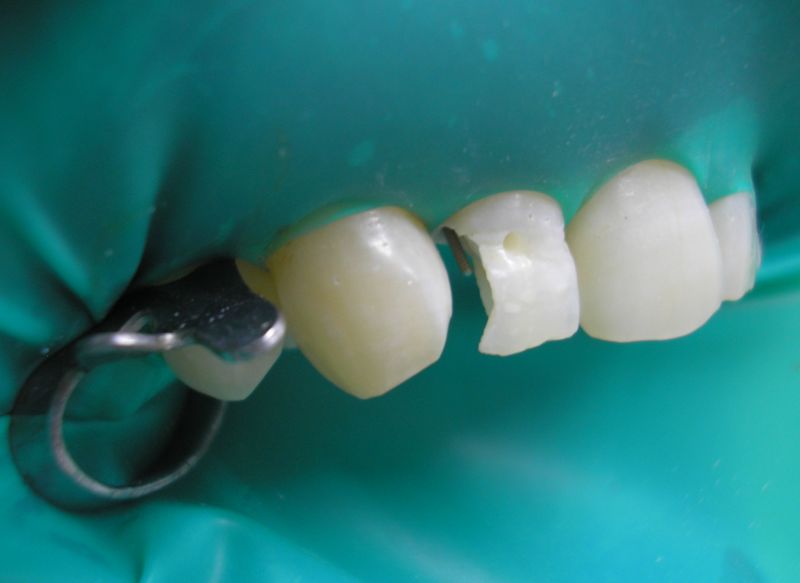

Tavaline (längnurgaga) preparatsioon on näidustataud

ulatuslikul kaarieskahjustusel, mis haarab lisaks kontaktpinnale ka hambanurka

(klassikaline IV klassi kaviteet).

Selline kaviteet vajab täidise püsivuse suurendamiseks

lisaretentsioone. Lisaretentsiooniks võib kasutada gingivaalset

retentsioonivagu (sügavusega umbes 0,25 mm), intsisaalset õnarust,

parapulpaarseid tihvte,

tappühendust (nõnda nimetatud pääsusaba preparatsioon

lingvaalsele hambapinnale) või nende omavahelisi kombinatsioone.

Tavalise meetodi puhul on oluline kasutada mõnda lisaretentsioonielementi: gingivaalset vagu, parapulpaarseid tihvte või tappühendust.